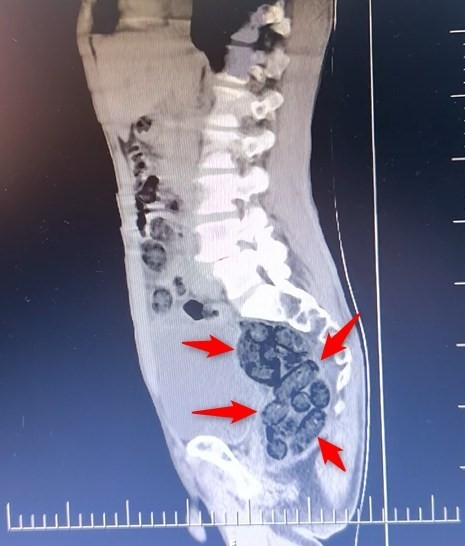

Durumundan şüphelenilen yabancı uyruklu bir yolcu üzerinde arama yapıldı. Yapılan incelemeler sonucunda yabancı uyruklu şahsın midesinde 64 Parça halinde toplam 472 gram uyuşturucu maddesi metamfetamin olduğu belirlendi.

Gözaltına alınan şahsın midesindeki uyuşturucu madde çıkartıldı. Emniyetteki işlemlerinin ardından adliye sevk edilen şahıs, çıkarıldığı mahkemece tutuklanarak cezaevine gönderildi.